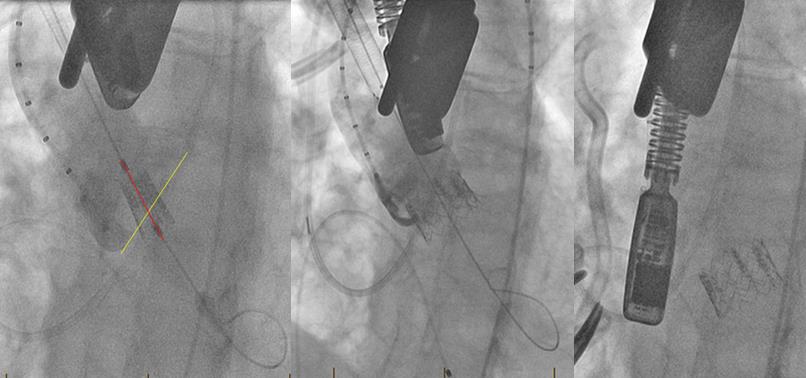

Fig. 9: Intraoperative angiograms from a case complicated by valve embolization. The wire is not coaxial with the native annulus (left). The valve is deployed in a canted fashion—50/50 on the non-coronary cusp and 10/90 on the left coronary cusp (center). Prior to removal of the sheath, the valve embolized into the ventricle (right).